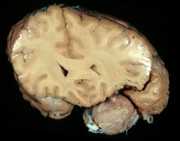

28

C. Benign supratentorialextra-axial tumor.